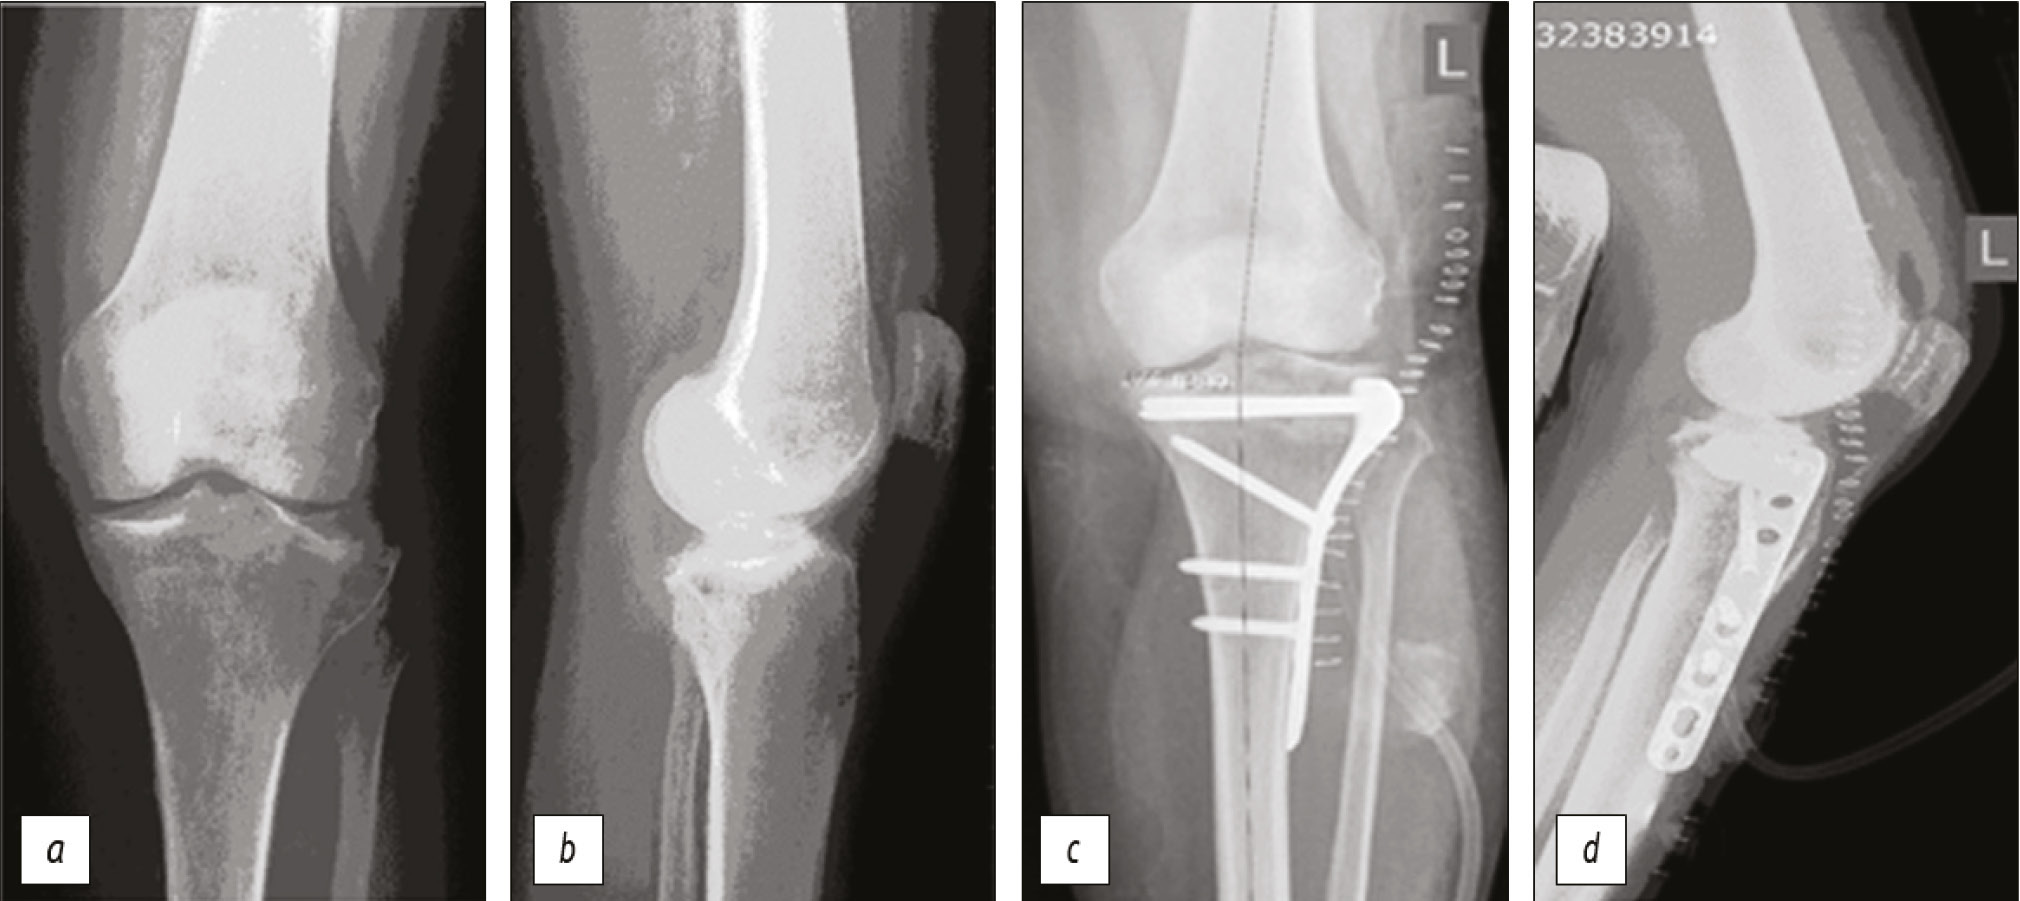

Surgical technique. In the case of valgus deformity, intra-articular osteotomy of displaced osteocartilaginous fragments with bone defect replacement with an allograft and fixation with locking compression plate proximal tibia plate was most often performed (n=25) (Fig. 1).

Figure. Radiographs of the knee joint of a 65-year-old female patient: a, b — on admission: malunion of the proximal tibia fracture. On radiographs of the knee, valgus deformity with impression of the lateral condyle of the tibia was determined; c, d — intra-articular osteotomy of the posterior and central part of the lateral condyle was performed, osteotomy and reduction of the osteochondral fragment, filling of the bone defect formed during the elevation of the articular surface with an allograft, fixation with an LCP PTP. The congruity of the articular surface was restored, the deformity was corrected.